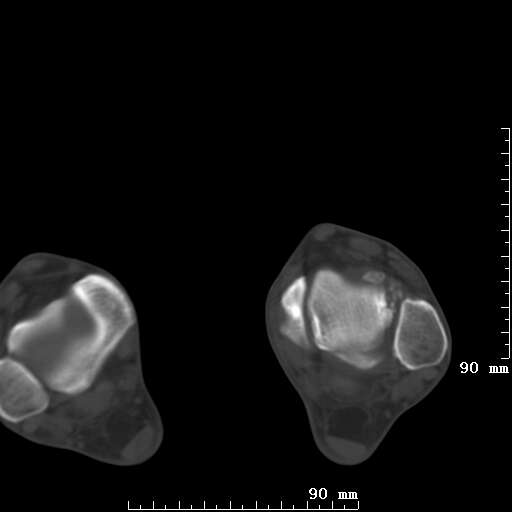

标题: CT19820:外伤一天,如何定性.男27Y [打印本页]

标题: CT19820:外伤一天,如何定性.男27Y

排除下创伤性关节炎吧,距骨有些囊变和硬化,周围韧带软组织有些机化、钙化。不是很像距骨无菌性坏死,感觉在关节面上的多,而不是距骨里面。

未见骨折及脱位像。距骨像是剥脱性软骨炎

支持!(踝关节距骨表面囊变和硬化 缺损)

距骨剥脱性软骨炎可能;踝关节创伤性关节炎?

未见明确新鲜骨折改变,距骨剥脱性软骨炎或踝关节创伤性关节炎可能。